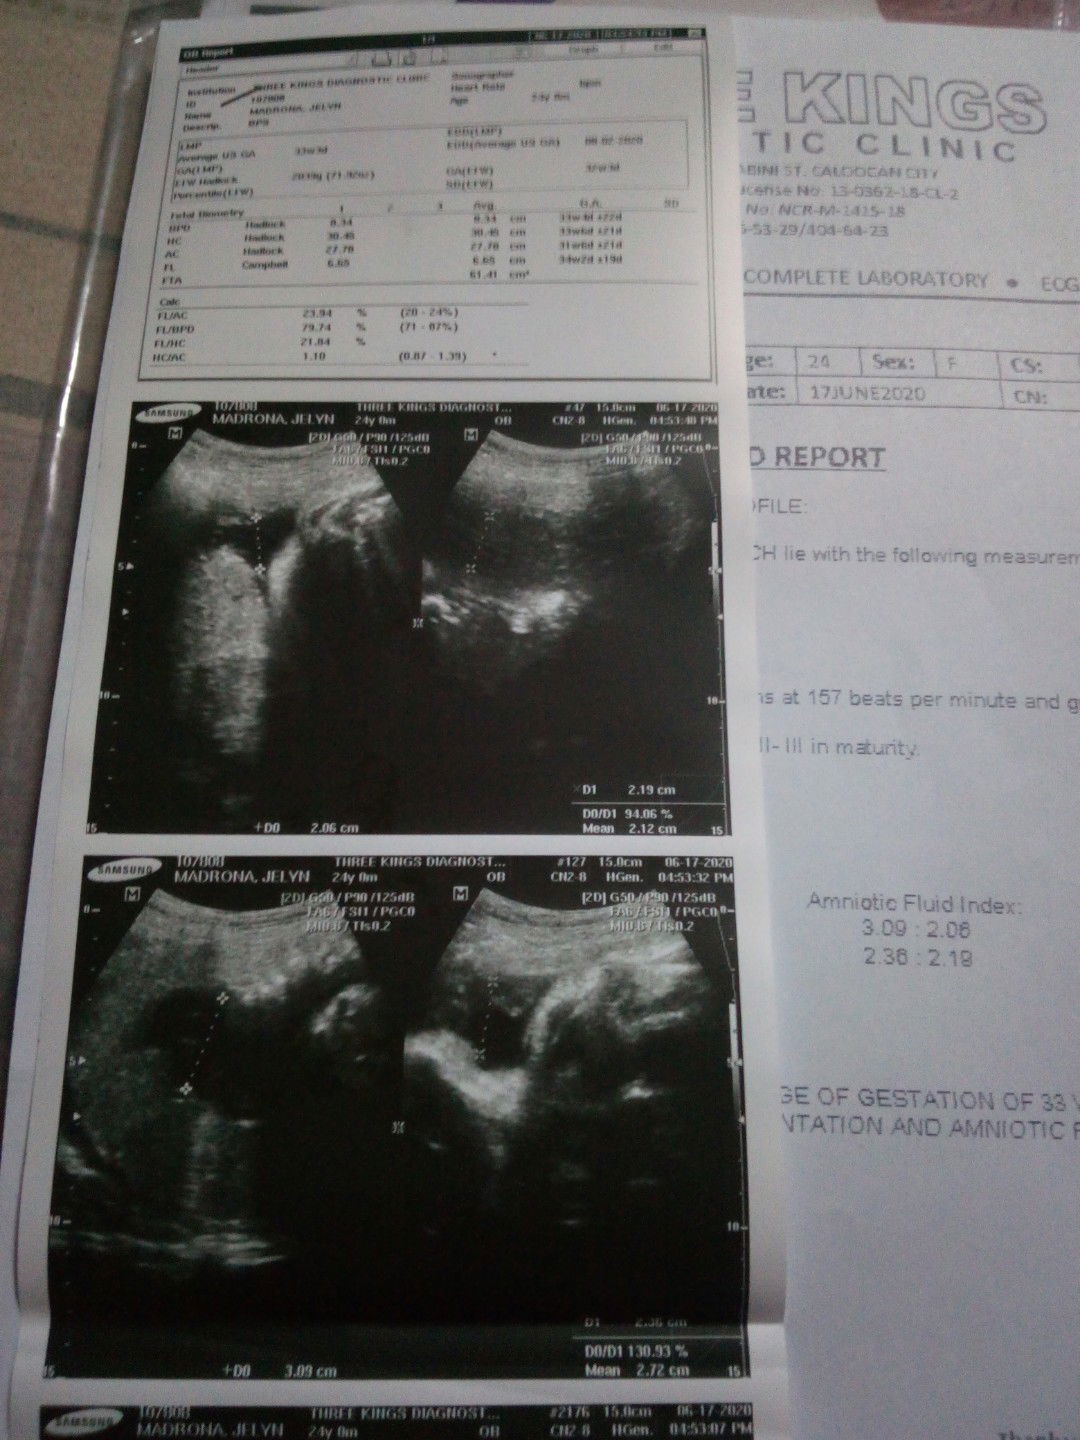

Hi po mga momsh pangalawang ultrasound ko na po kanina kaso nakabreech position pa din siya kaya di makita ang gender niya 8mos preggy po ako may chance pa bang magbago ang position niya once na lalabas siya? Saka po kapag breech po position si baby maglalabor pa din po ba? Pa advise naman po kung ano pwede gawin para ma normal ko si baby Salamat sa sasagot☺️